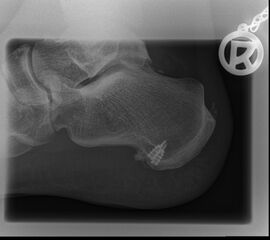

Abb. 9a–d: chron. Plantarfasziitis mit plantarem Fersensporn und Irritation Baxternerv plantar lateral

Kasuistik: 28-jähriger Patient, Profisportler.

Abb. 9a: Plantarer Fersensporn und Plantarfasziitis im MRT prä-op.

Abb. 9b: Plantarer Fersensporn im CT prä-op.

Abb. 9c: Lateraler Zugangsweg bei atypisch weit nach plantar lateral liegendem Sporn.

Abb. 9d: Röntgenkontrolle nach Minioffenem Plantarfaszienrelease und Abtragung Fersensporn mit Neurolyse.

Zum Lesen der Bildbeschreibung und zur Vollansicht bitte die Bilder anklicken. Bilder: Manfred Thomas.